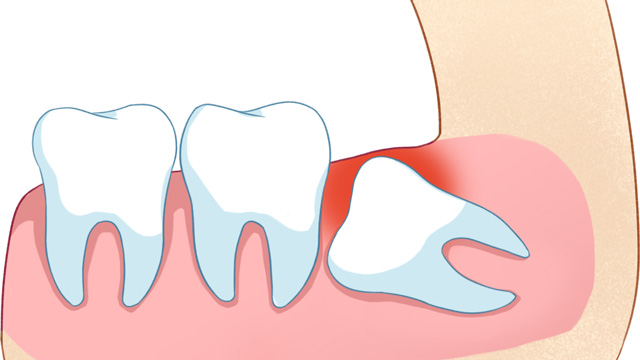

03智齿位置不正,未来存在潜在风险

有些智齿虽然目前没有疼痛、没有挤压邻牙,但拍X光片后发现,它属于“埋伏阻生”(完全埋在牙龈下),或者生长方向异常,未来很可能会萌出、挤压邻牙,甚至引发囊肿、肿瘤等问题。对于这类堪比“定时炸弹”的智齿,医生通常会建议拔除,避免后续出现更严重的口腔问题。